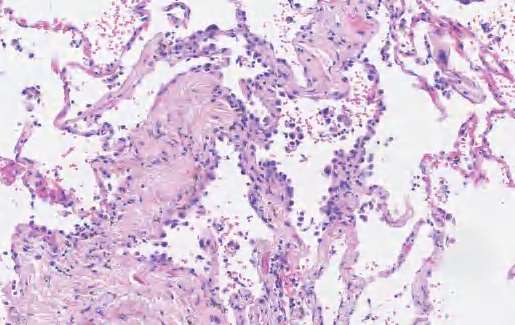

【镜下形态】几乎所有AIS均为非黏液性,通常表现为Ⅱ型肺细胞和(或)Club细胞沿原有肺泡壁连续单层增生,有时可见细胞重叠或轻度分层或微小细胞簇生成,但不存在浸润性生长模式(如腺泡、乳头、微乳头、实性和肺泡腔内存在肿瘤细胞)(图2-2),也不存在间质、脉管、胸膜的浸润及气道播散(STAS)现象。事实上,AIS常存在组织形态改变的多样性,某些区域肿瘤细胞处于缓慢生长或静止甚至退缩状态,肿瘤细胞由于自身凋亡,细胞数量减少,肺泡张力减小,难以维持肺泡结构,伴随肺间隔纤维组织增生,导致部分AIS的腺体内陷,但并非真正的浸润。有些AIS的局部区域肿瘤细胞明显增殖活跃,表现为肿瘤细胞核增大、深染,并突向肺泡腔,但不见核仁,常可见核内包涵体。有时由于切面或制片,可以形成少量的假乳头,这些假乳头成分不是真正的具有二级和三级分支的乳头状结构,因此不能视为浸润性成分。

图2-2 AIS